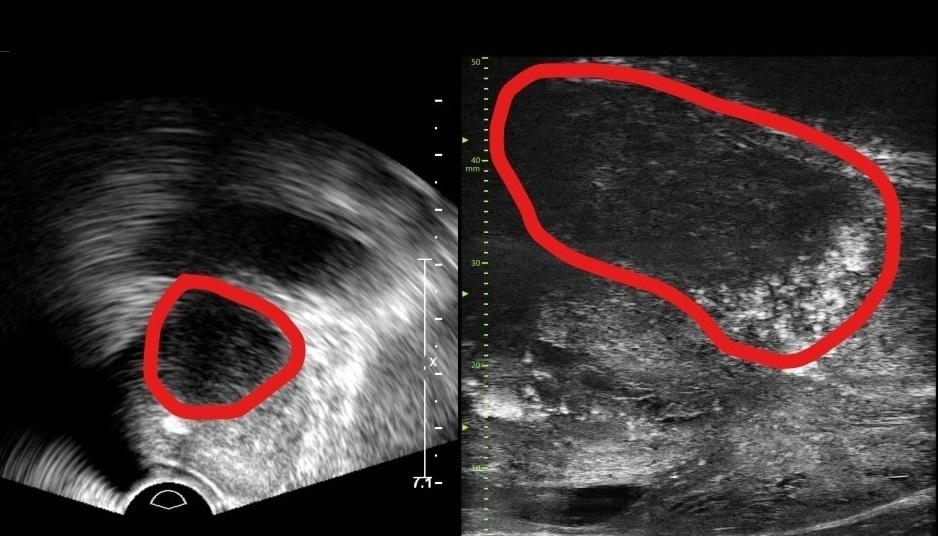

29MHz 마이크로 초음파를 사용하는 이 장비는 전립선과 주변의 해부학적 구조를 선명히 표시하고 표적 조직검사를 유도한다. 의심 영역을 실시간으로 확인하면서 전립선 조직의 미세한 변화와 병변을 식별하고 조직검사 채취를 위한 바늘을 정확한 위치에 삽입할 수 있다는 장점이 있다.

또한 전립선암 진단을 위한 초음파 검사 가이드인 PRI-MUS(Prostate Risk Identification Using Micro-Ultrasound) 위험도 식별 시스템과 연계돼 있어 전립선암 병변의 악성 가능성 평가는 물론, 어느 부분에서 조직을 채취해야 하는지 정확히 판단할 수 있게 한다. PRI-MUS는 초음파상 병변의 모양이나 크기를 자동으로 판단해 병변의 악성도를 1~5단계(높을수록 위험)로 분류하기 때문에 불필요한 조직검사를 줄이면서도 암을 놓치지 않게 돕는다.

기존의 경직장 초음파는 해상도가 낮아 전립선 종양, 특히 작은 암 병변을 감지하는 데 한계가 있었다. 하지만 마이크로 초음파의 높은 해상도와 실시간 영상의 시각화는 자기공명영상(MRI)으로 발견할 수 없는 전립선암을 찾을 때도 충분히 기여할 것으로 기대하고 있다. MRI 검사 보다 환자의 신체적, 심리적, 경제적 부담도 적다.